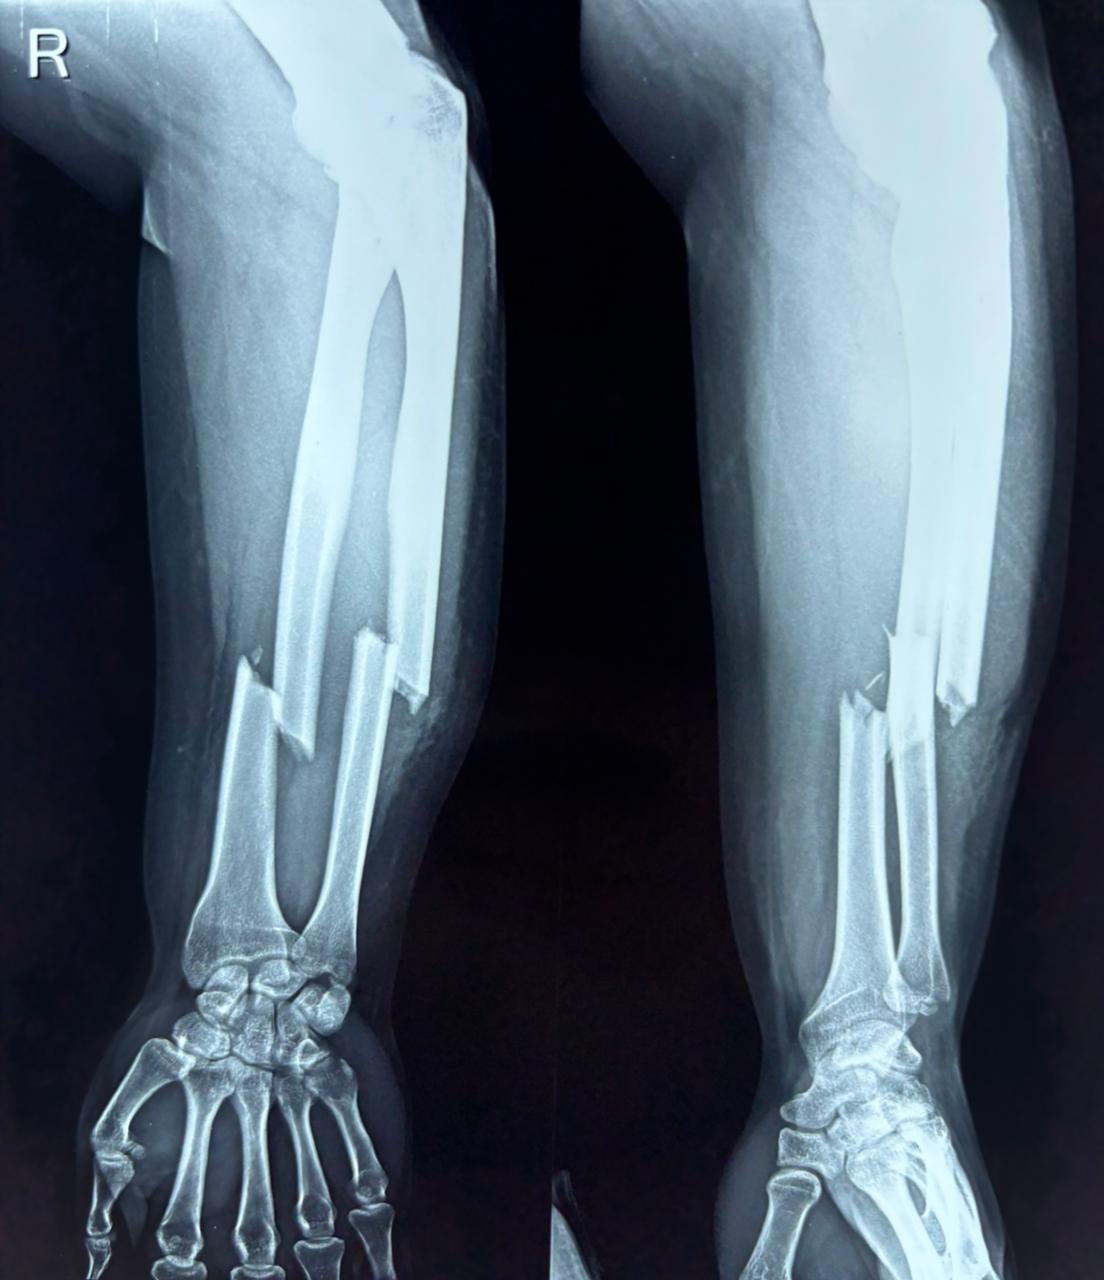

Radial Neck Fracture - Paediatric

This X-ray demonstrates a radial neck fracture in an 8-year-old child, visible on both AP and lateral views of the elbow. The fracture occurs at the junction of the radial head and radial shaft, with angulation...

By The Bone Stories 1 images